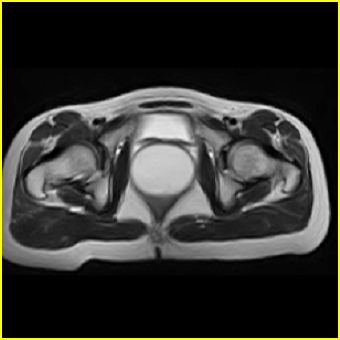

女、15岁、下腹疼痛2天,排尿困难1天。查体:处女膜闭锁,距处女膜约4至5cm处扪及一约5cm直径的圆形包块,张力较高,触痛明显、欠活动。b超提示子宫增大伴宫内增强回声团。

影像意见:子宫直肠陷凹积血。

更正影像意见:阴道积血。

处女膜闭锁,阴道积血

处女膜闭锁,阴道积血,子宫积血.

先天性处女膜闭锁,伴阴道积血,不除外先天性阴道粘液囊肿形成。

阴道积血,子宫积血.

子宫及阴道积血。

处女膜闭锁,伴子宫及阴道积血.